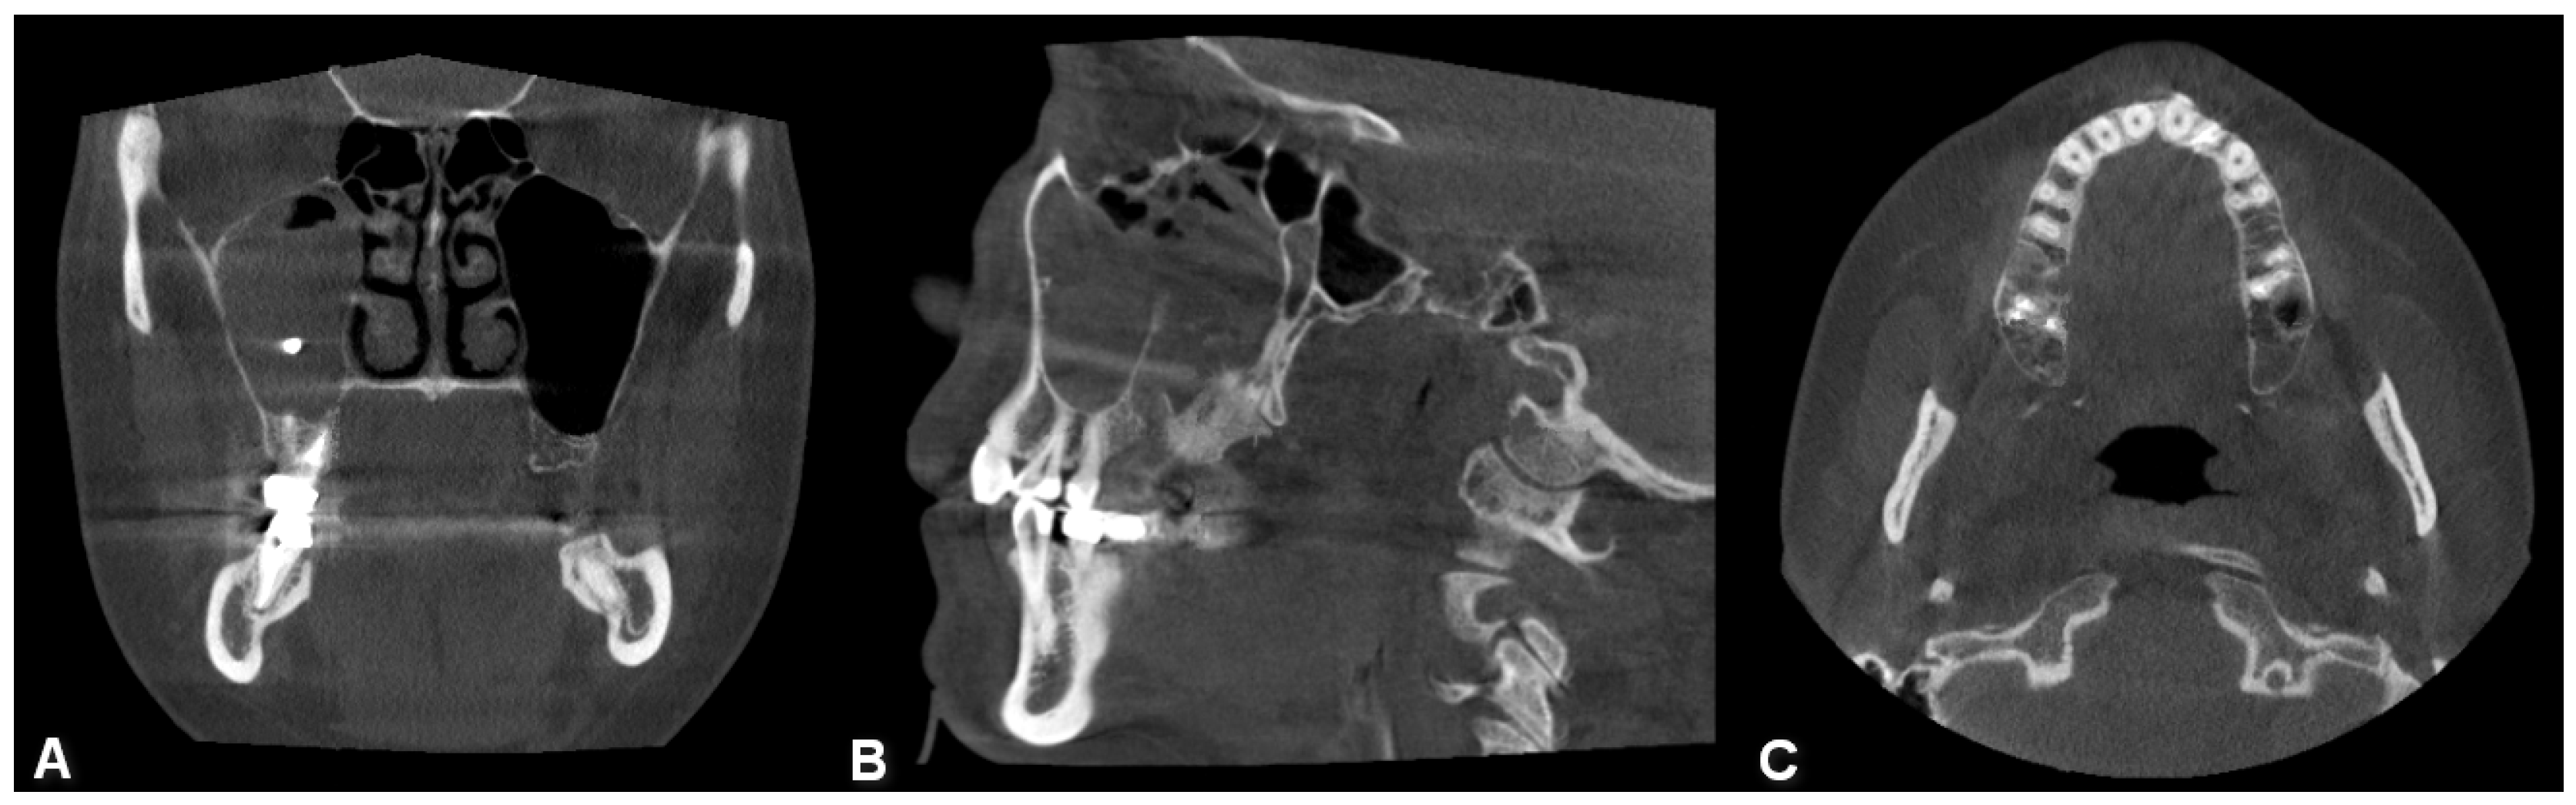

Figure 7. CBCT image of bilateral maxillary sinusitis caused by blade implants; chronic OAF (oroantral fistula) next to the implants. ((A): coronal, (B): sagittal, (C): axial view).